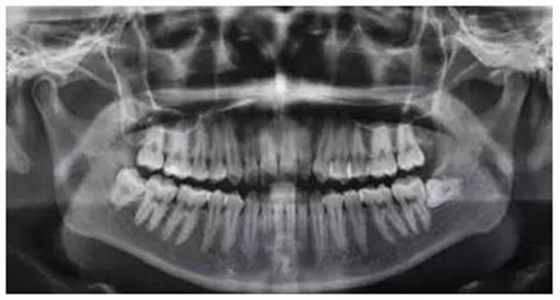

圖1.術(shù)前的患者的全景片影像檢查:48合面平齊區(qū)7牙頸部。

圖2.全景片局部放大影像:48融合根、牙根未發(fā)育完成,牙周膜清晰。

(1)根據(jù)全景片影像檢查:48牙冠合面平齊牙頸部,但牙根未完全發(fā)育完成,患者年紀(jì)尚小,屬于最佳拔牙年齡。故采用小切口,不附帶垂直切口

(5)該病例牙根呈錐形、牙根未發(fā)育完成、遠(yuǎn)中牙囊影比較明顯,故不用分牙,直接用挺拔除。